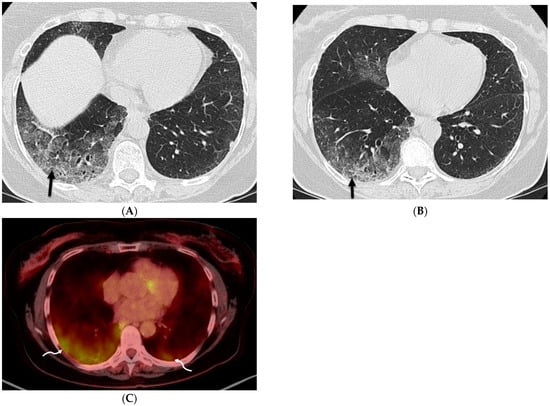

6.2. Pulmonary Alveolar Proteinosis (PAP)